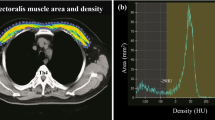

Measurement of pectoralis muscle index (PMI)

We measured the right pectoralis muscle area [cm2] at baseline and follow-up CT scans using CORESLICER, a validated web-based application for accurate assessment of muscular body composition [14]. Two readers (JW, CG) reviewed a single axial slice of chest CT above the aortic arch. Once the appropriate axial slice was found, readers used the software’s shading function to estimatearea (cm2) of the right pectoralis major and minor muscles. These raw pectoralis measurements were then indexed to the height square to calculate PMI (PMI: pectoralis muscle area [cm2]/body height2 [m2])).